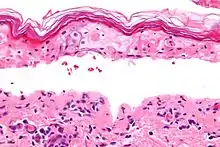

Micrografía mostrando el grosor de la necrosis epidérmica con un estrato córneo con aspecto de tejido de esterilla y separación de la dermis y la epidermis. Biopsia de la piel. Tinción hematoxilina-eosina.

El síndrome, al igual que la necrólisis epidérmica tóxica y el eritema multiforme, está caracterizado por la confluente necrosis epidérmica con la inflamación mínima asociada. La agudeza es evidente observando el patrón de la capa córnea.

Desde el punto de vista patológico, el hallazgo más característico es la necrolisis epidérmica, espongiosis, edema intracelular, cambios vacuolares en la unión dermoepidérmica, edema y extravasación de eritrocitos. La biopsia de piel puede confirmar el diagnóstico.